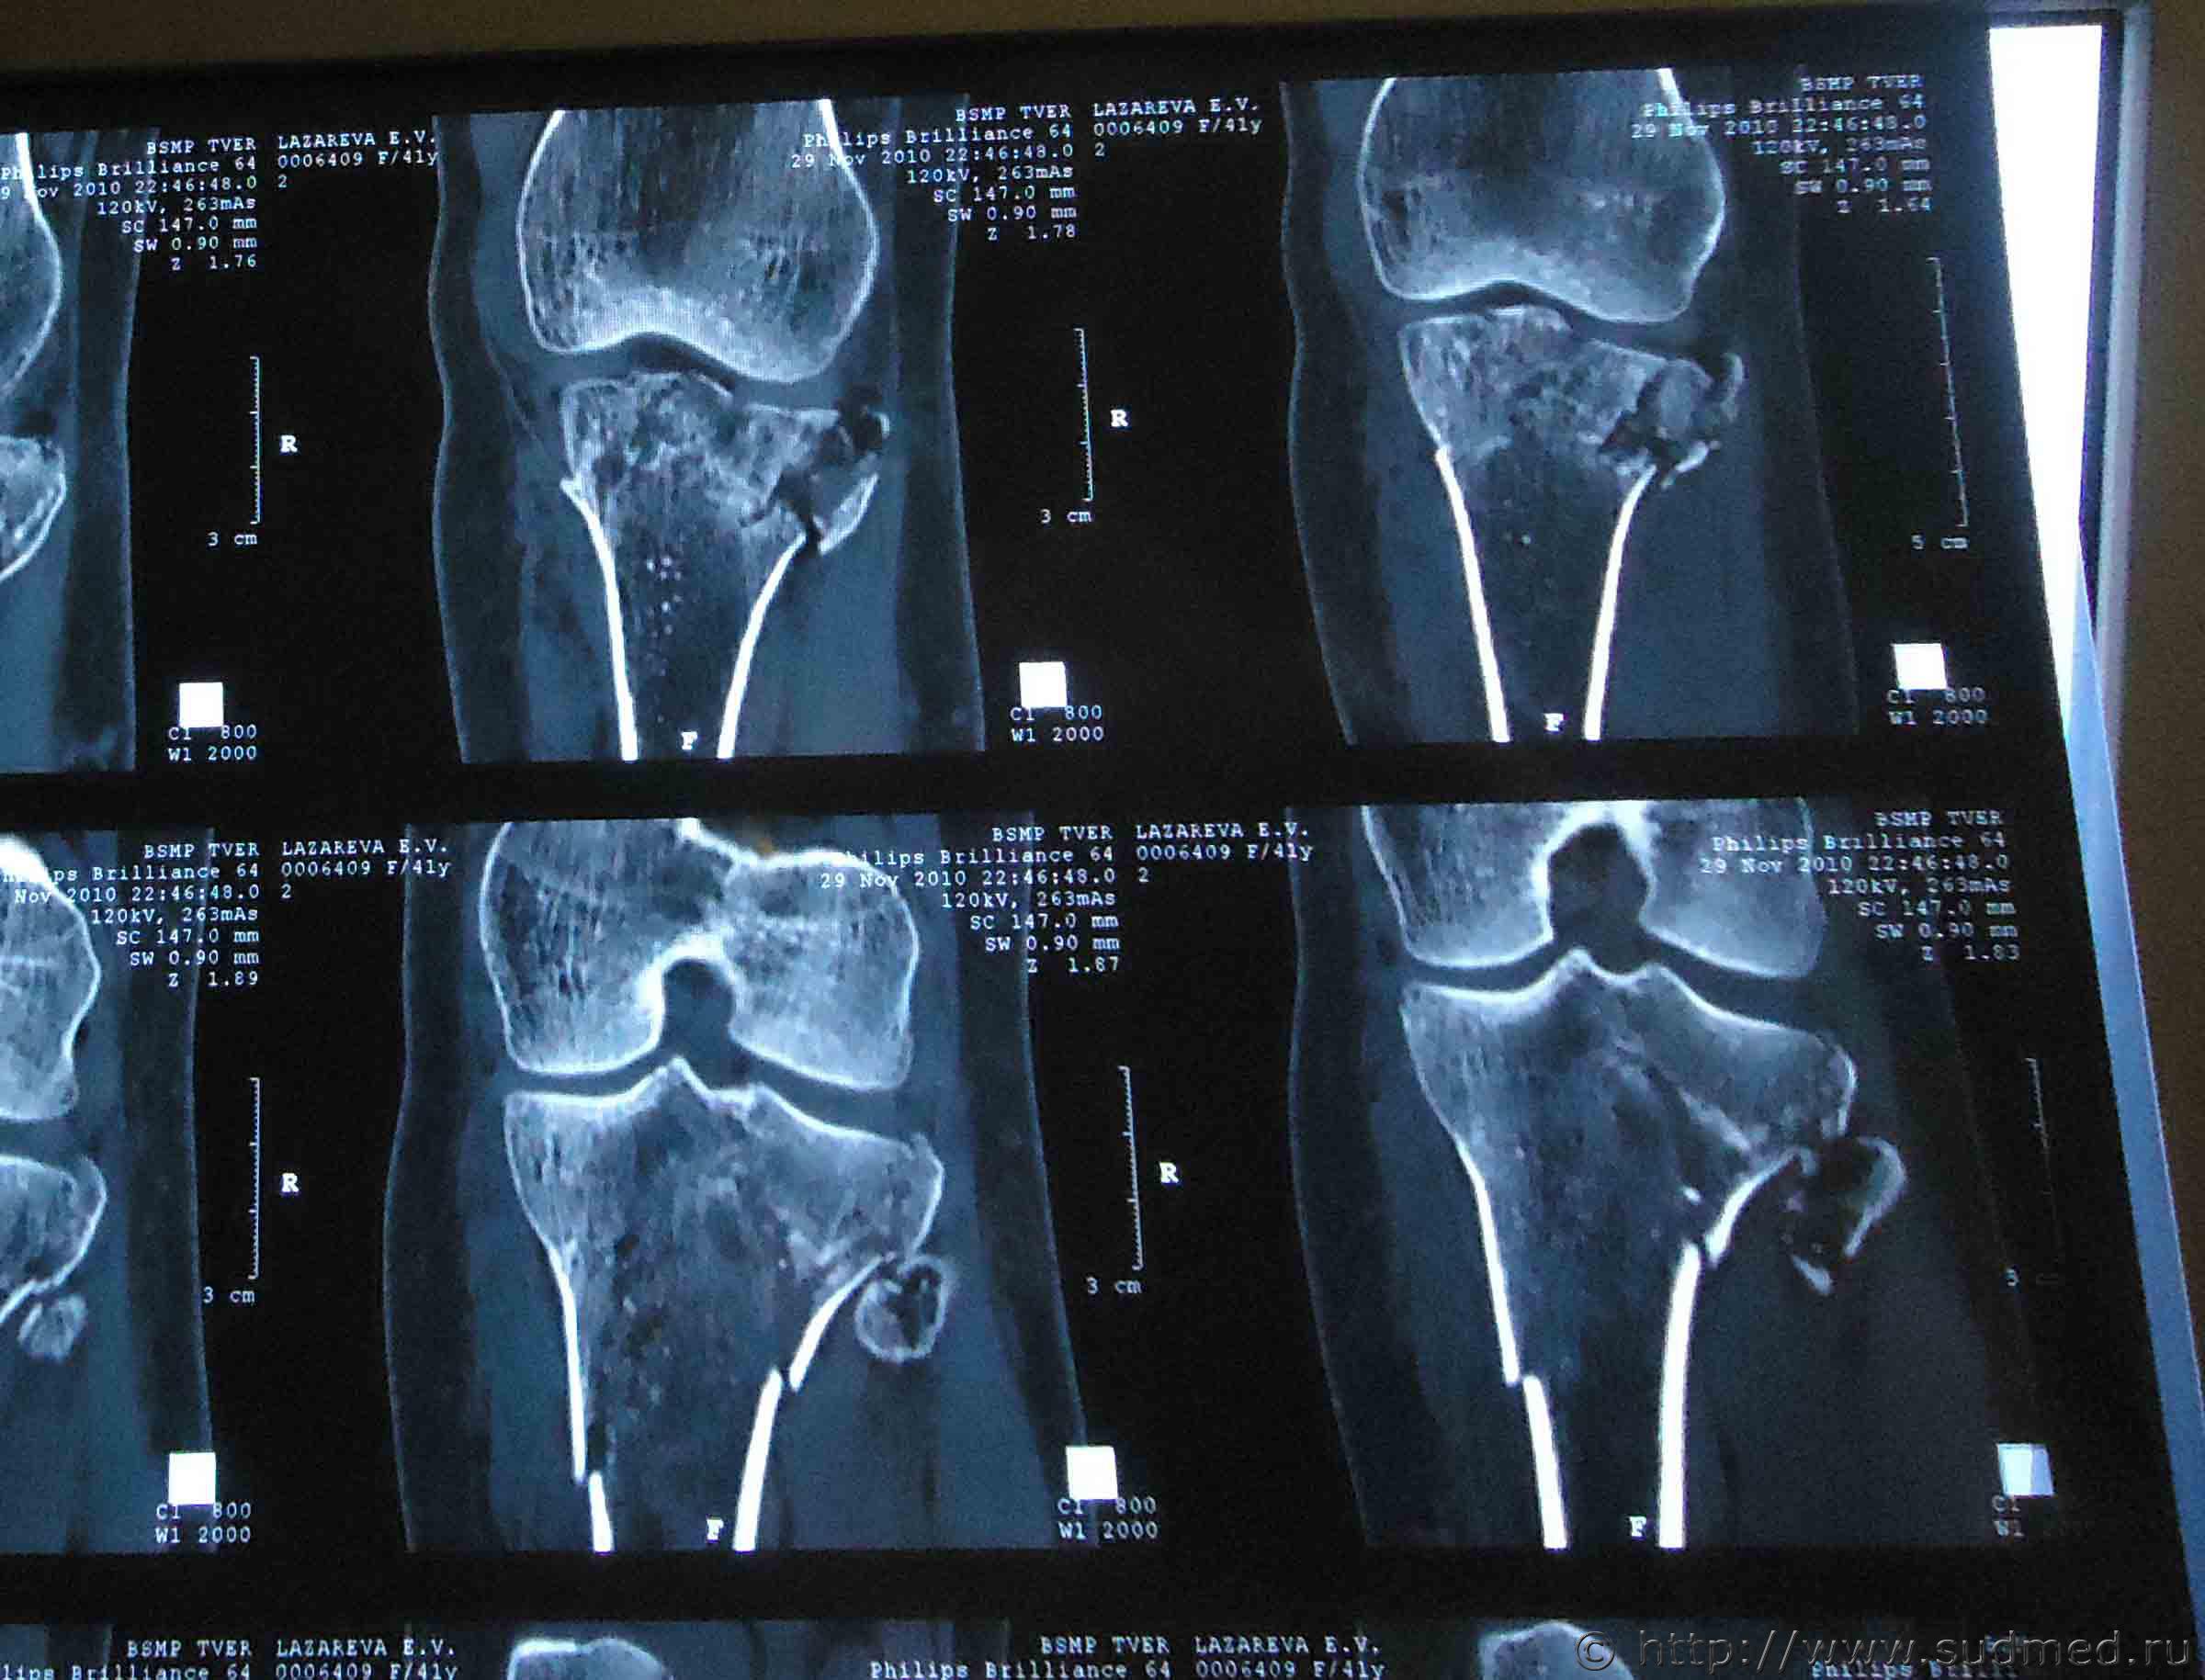

Здравствуйте. На мою жену 2 года назад был совершен наезд, при этом она получила травмы: ЗЧМТ, сотрясение головного мозга, закрытый оскольчатый внутрисуставной перелом проксимального метаэпифиза левой большеберцовой кости со смещением, закрытый оскольчатый перелом проксимального эпифиза левой малоберцовой кости без смещения, закрытый косой перелом правой ключицы средней трети со смещением отломков.

Помогите установить степень тяжести вреда и что делать для обжалования медицинской экспертизы? Снимки прилагаю